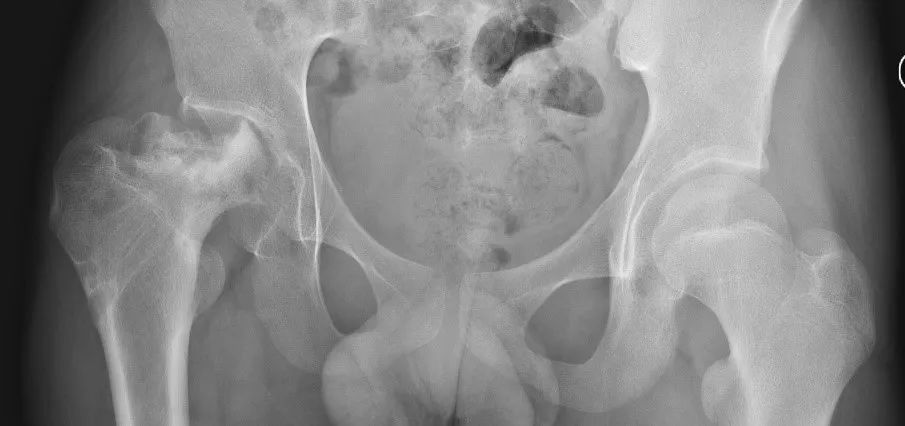

左侧发育性髋脱位治疗后,半脱位合并股骨头缺血坏死表现